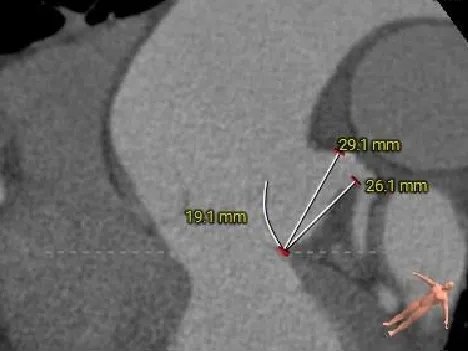

左室测量

舒张期大左室,典型关闭不全引起的心室扩张